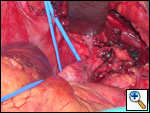

| Figure 1 |

On physical exam the patient had an obviously swollen head without cyanosis, but with multiple collaterals over her chest and upper neck. An MRA was obtained which demonstrated complete obstruction of the superior vena cava below the brachiocephalic junction (Figure 1). There were also significant collaterals through the intercostals and internal mammary veins, but no evidence of intrathoracic mass, adenopathy, or evidence of vein thrombosis.